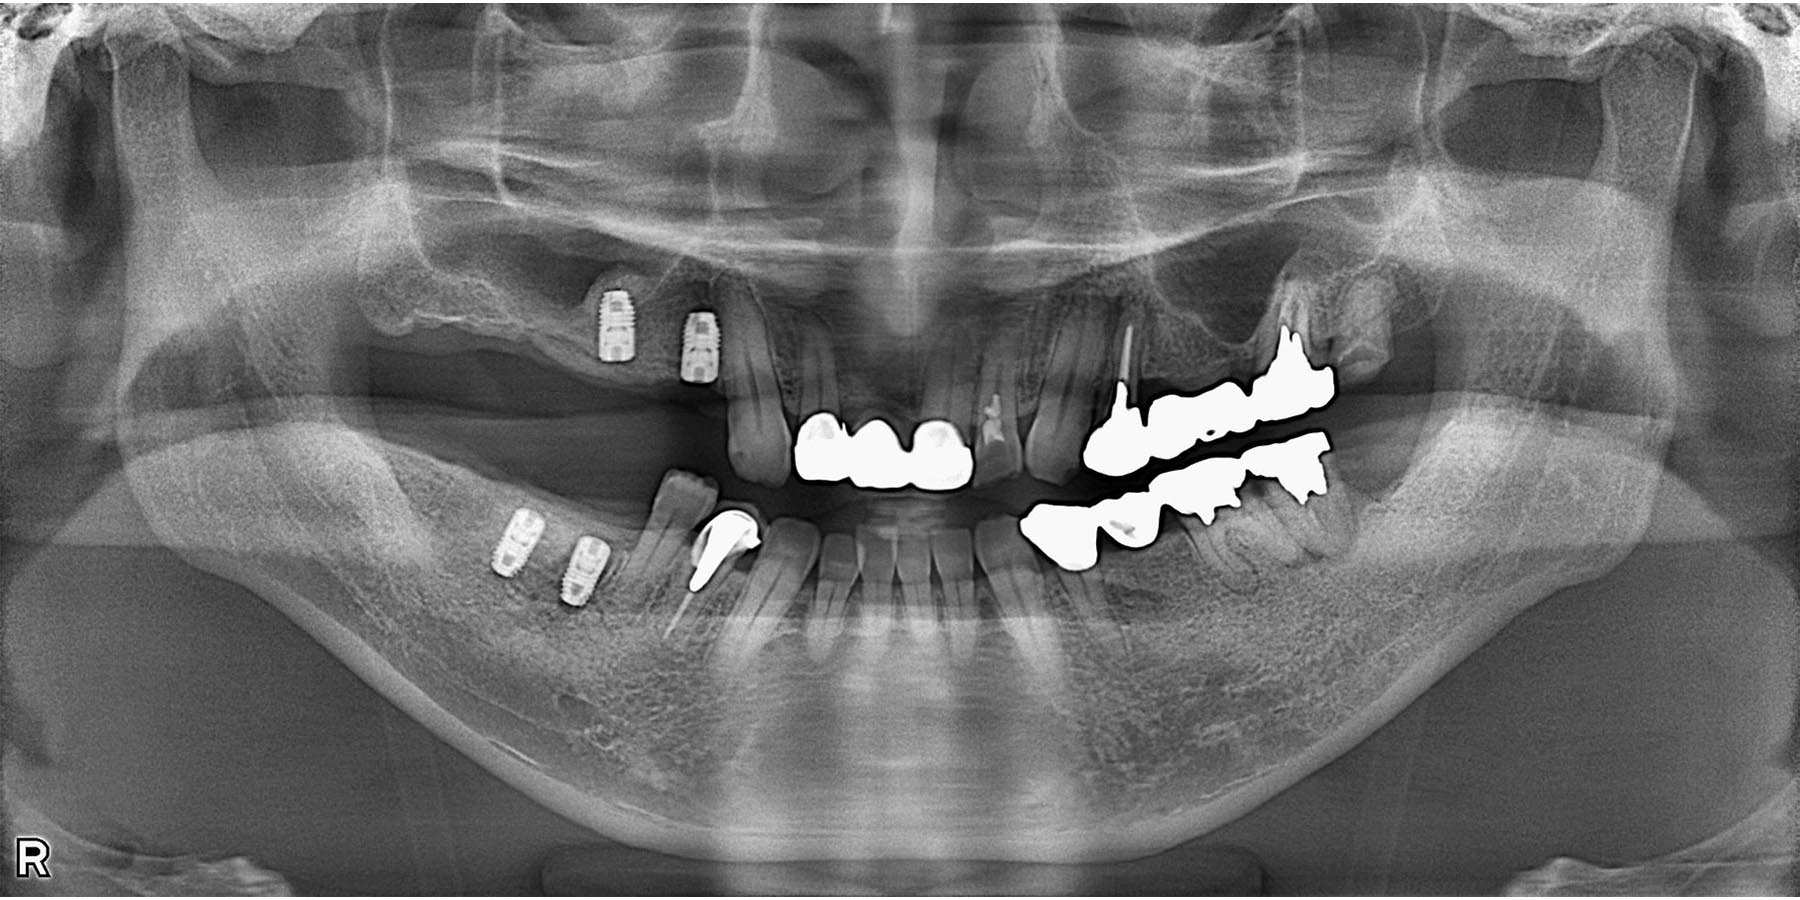

治療後

インプラント埋入後

被せ物セット完了

| 治療内容 | 麻酔科認定医による静脈内鎮静下で右下6.7、右上4.6のインプラント治療(4本) 右上6部は骨不足のためソケットリフト |